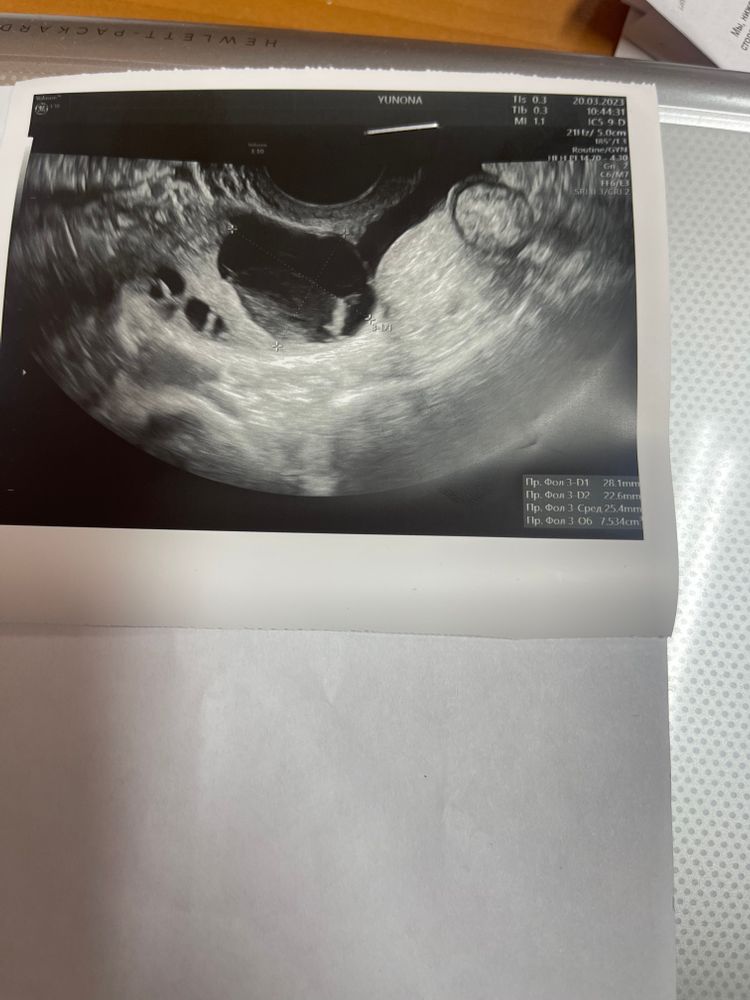

Галина, тогда очень сомневаюсь что за 4 дня фолликул вырос больше 25мм. Ну даже если в среднем рос по 2мм в сутки с 14мм он дорос бы до 22мм а это нормальный размер. У вас есть заключение, что там написано конкретно, есть размеры?

Екатерина, там написано по 10 фолликулов от 4 до 7мм в обоих яичниках,но а в правом киста ещё,размеры ее не написаны

Галина, 28 на 23 мм - мне кажется, это как раз размеры кисты

Галина, может быть киста желтого тела и овуляция как раз прошла? Что-то про жидкость в позадиматочном пространстве при слова не увидела, есть она или нет

Галина, видела узи. По размерам да, киста…но фолликулярная ли?

Возможно это фолликулярная киста, то есть если фолликул больше 26мм,его уже описывают к стой. Какие вам размеры написали?

Галина, непонятно почему структура в виде ячеек и кровоток есть, так обычно у жёлтого тела. Думаю нужно переделать через пару дней, размеры в любом случае не опасные, рассасется. Или если продолжит расти, то попить дюфастон для вызова месячных и месяц фемостон попить. Мне так назначили.